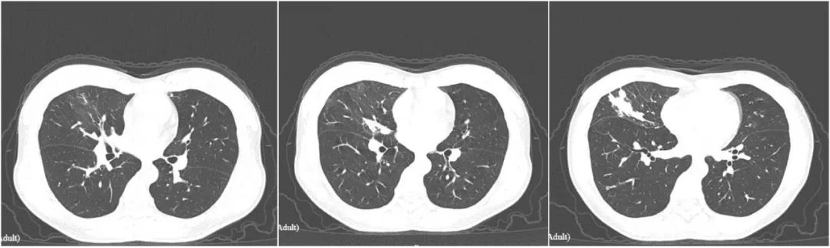

现病史:此次咳嗽咳痰再次出现入院,痰色白,无畏寒发热,无明显胸闷气急,无胸痛咯血等表现。肺CT提示“右肺中叶感染性病变伴部分支气管闭塞,较前(4月前)左肺上叶感染已基本吸收,右肺中叶感染有吸收,两肺散在增殖灶”。支气管镜检查:右肺中叶外侧支痰栓阻塞,开口略狭窄。右肺中叶外侧支肺泡灌洗液送检病原学检查

此次CT: